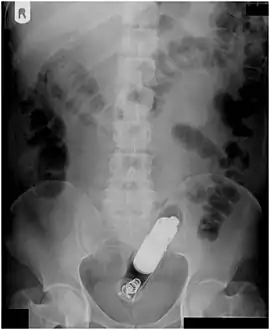

| Radiograph of a male abdomen with a vibrator inside the rectum | |

Usually, several radiological images are recorded in order to pinpoint the precise place and depth of the foreign body. This is usually done by X-ray. Foreign bodies made from low-contrast material (e.g. plastics) may necessitate medical ultrasound or a CT scan.[29] Magnetic resonance imaging is contraindicated, especially if the foreign body is unknown. Foreign rectal bodies may penetrate deep into the colon, in certain circumstances up to the right colic flexure.[10]